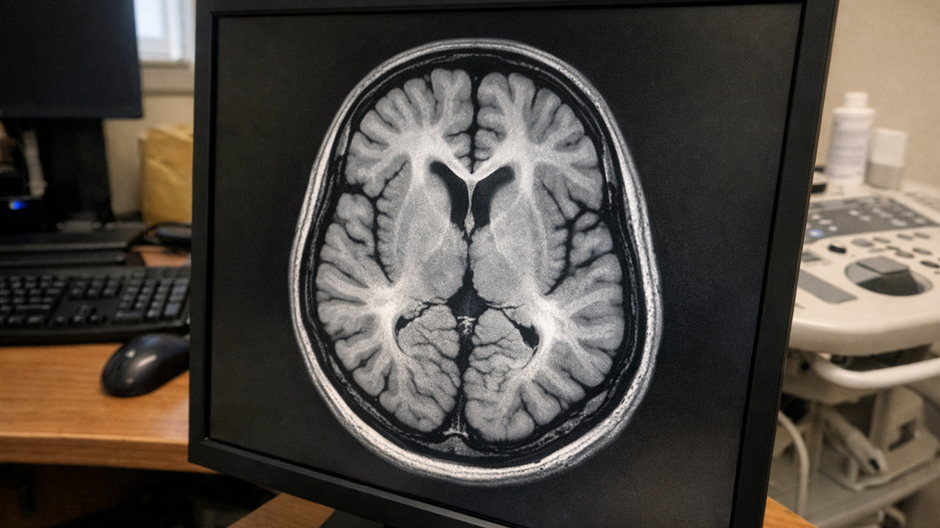

Vysokorozlišovacia klinická MRI snímka ľudského mozgu zobrazujúca detailnú štruktúru šedej a bielej hmoty s výrazným anatomickým kontrastom na tmavom radiologickom pozadí.

Zdroj: Freepik.com

Austrálski vedci zistili pomocou magnetickej rezonancie, že covid môže zanechať merateľné zmeny v mozgu – dokonca aj u ľudí, ktorí nemali žiadne príznaky. Ide o malé, ale významné rozdiely v štruktúre a metabolizme mozgového tkaniva.

Tím z Griffith University v Austrálii skúmal pomocou MRI štruktúru šedej a bielej hmoty mozgu. Šedá hmota súvisí s pamäťou, myslením a spracovaním informácií, biela hmota zabezpečuje prepojenie medzi jednotlivými oblasťami mozgu. Práve tieto dve kľúčové oblasti vykazovali rozdiely medzi ľuďmi po prekonaní infekcie a kontrolnou skupinou.

MRI snímky ukázali zmeny v chemickom zložení mozgu aj v štruktúre tkaniva. U pacientov s dlhodobým covidom boli tieto rozdiely výraznejšie a súviseli so závažnosťou symptómov. Vedci zároveň zaznamenali metabolickú nerovnováhu, ktorá sa u zdravých osôb nevyskytovala.